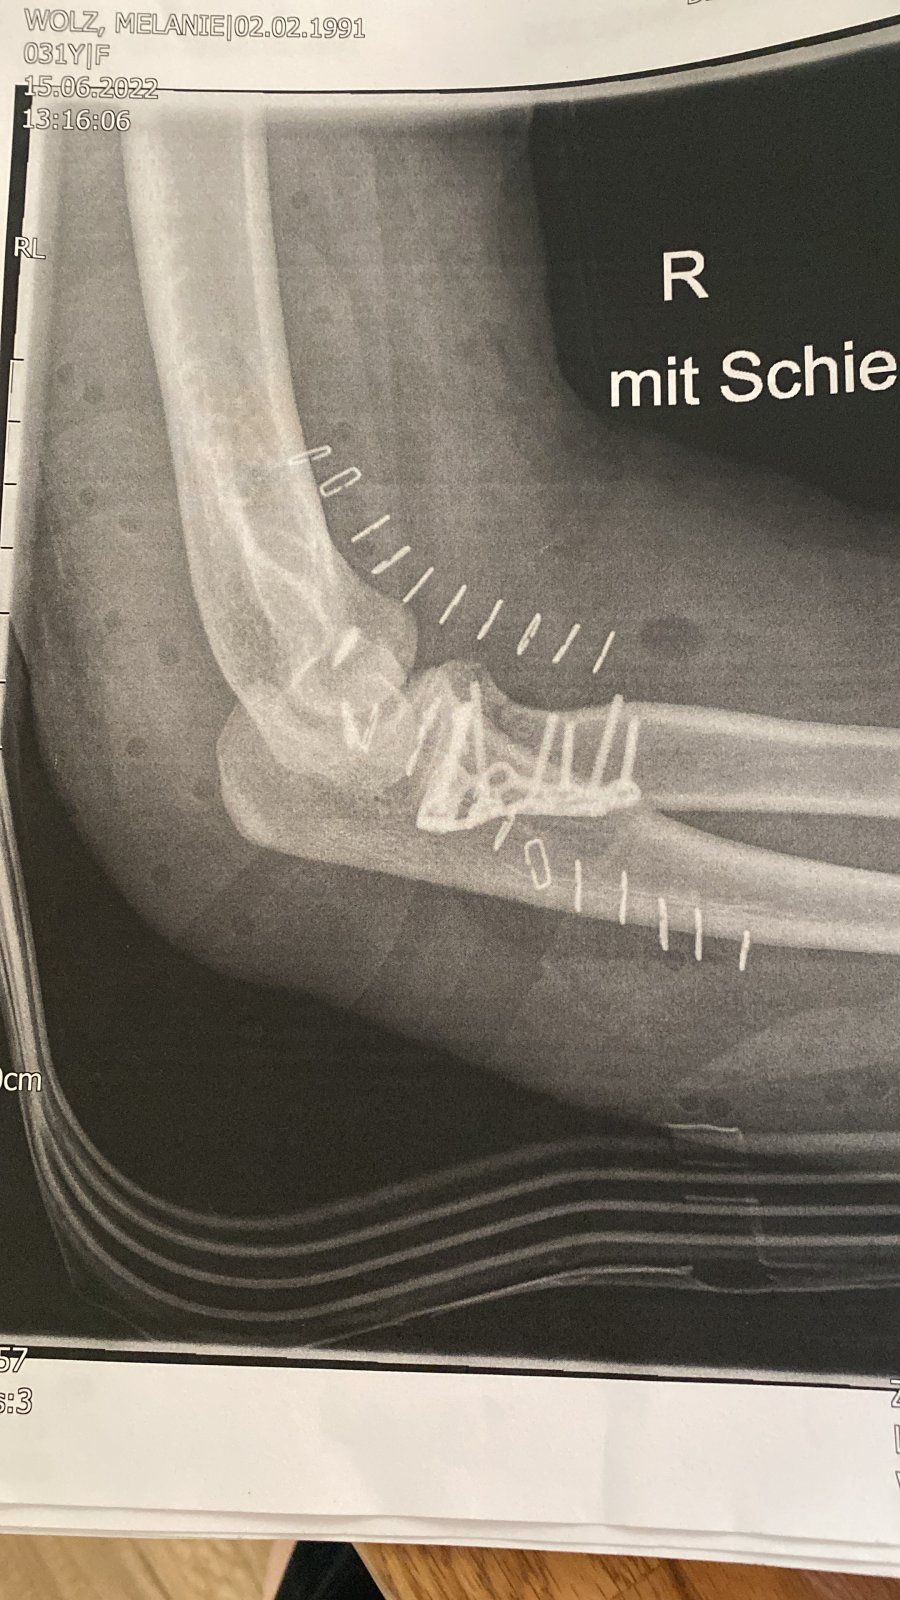

Hallo zusammen, hier scheine ich ja im richtigen Thread zu sein. Vielleicht gibt es Erfahrungswerte zu folgendem Fall. Habe mir das innere Seitenband im Ellenbogen gerissen und einen Muskelfaserriss zugezogen. Am Knochen wurde eine Fisur fest gestellt. Das Ganze ist jetzt 8 Wochen her. Nach einer etwas seltsamen Reise von Arzt zu Arzt hiess es letzendlich es wird nicht operiert. Ich mach 3x die Woche Physio und mach die Übungen fleißig. Allerdings dauert es gefühlt eeewig den Arm wieder in die Streckung und Beugung zu bekommen. Es fehlen in der Streckung noch 25° und schmerzt dann im Gelenk. Und generell wird es nur langsam besser mit der Bewegung. Die Kraft im Arm ist nicht wirklich vorhanden. Nun meine Frage... ist so etwas bei Euch vollständig geheilt. Es kann bei einer konservativen Behandlung zu Instabilität kommen - gibt es da Erfahrungswerte? Gerade im Zusammenhang mit dem Biken und der Haltung auf dem Rad?